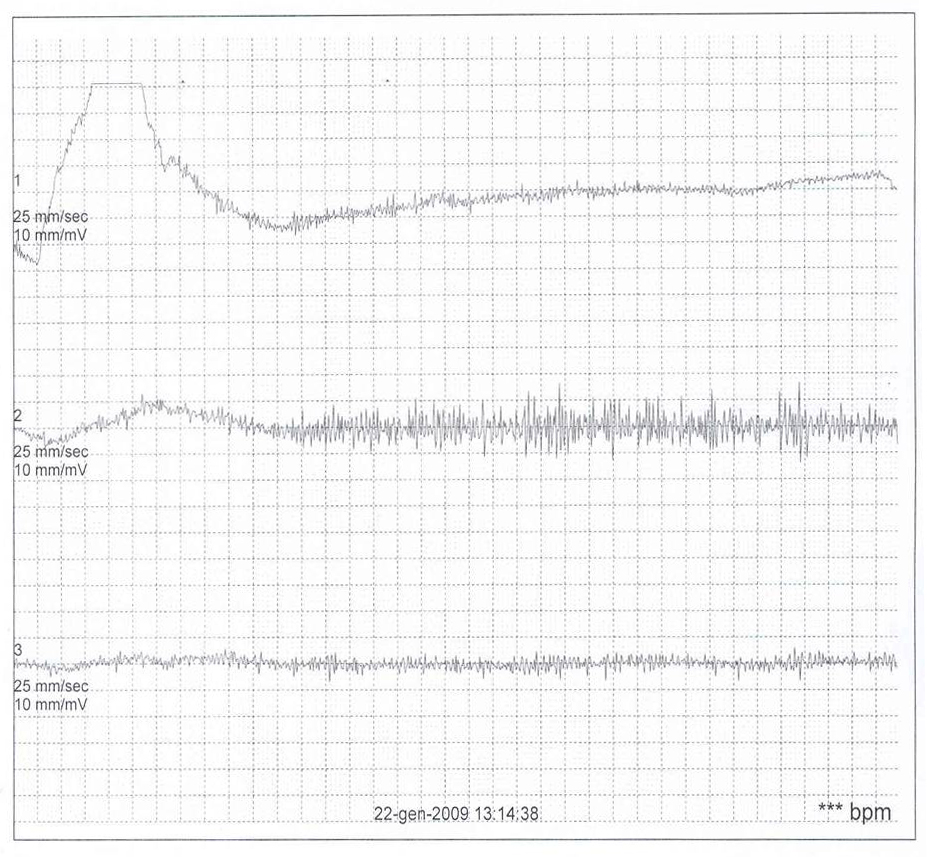

Una bambina di 13 mesi giungeva alla nostra attenzione per un episodio caratterizzato da �pianto senza rumore� (volto atteggiato al pianto senza emissione di voce), breve apnea seguita da pallore, rigidit� generalizzata per alcuni secondi, quindi perdita di coscienza con ipotonia generalizzata e pallore della durata di 3 minuti. L�episodio era stato innescato da una situazione di contrariet� espressa dalla bambina (si era opposta al tentativo di collocarla nel carrello del supermercato). In anamnesi venivano riferiti diversi episodi simili, tutti innescati da situazioni spiacevoli, fonti di contrariet�, rabbia, frustrazione o dolore fisico. L�esame obiettivo generale e neurologico era negativi. L�ECG con il QTc, l�ecocardiografia, l�EEG, la consulenza neurologica e la RMN dell�encefalo risultavano nella norma. La sintomatologia presentata dalla paziente veniva interpretata come spasmo affettivo di tipo pallido con sincope. Durante un ECG Holter 24 ore, in corrispondenza di alcuni episodi di spasmo respiratorio (spontanei o indotti riproducendo condizioni provocatorie di frustrazione o contrariet�), abbiamo registrato brevi fasi di asistolia (della durata massima di 4 secondi). Questo reperto ci ha fatto ipotizzare che l�asistolia alla base degli spasmi affettivi avesse una durata maggiore di quella da noi riscontrata.

Tale ipotesi � stata poi confermata da un nuovo ECG Holter 24 ore che ha evidenziato, durante uno spasmo affettivo pallido spontaneo esitato in sincope e crisi convulsiva generalizzata, un�asistolia di circa 25 secondi (Figura 1). � stata quindi iniziata terapia vagolitica con atropina solfato per os (0,01 mg/kg/dose per 2 somministrazioni/die) per contrastare l�iperreattivit� parasimpatica ritenuta responsabile dell�asistolia. Questa terapia si � rivelata inefficace. La bambina ha infatto presentato alcune recidive di spasmo respiratorio pallido, sincope e crisi convulsiva. Vista la sua particolarit�, il caso � stato discusso su un forum di cardiologia pediatrica accessibile in rete (Pediheartnet) da cui sono emersi sostanzialmente due progetti terapeutici: il primo, di maggioranza, raggruppava i fautori dell�impianto di un pacemaker ventricolare; il secondo, di minoranza, raggruppava i fautori di una terapia farmacologica con diversi farmaci come teofillina, clonidina, sertralina, cerotto di scopolamina, glicopirrolato. Anche alla luce di tali pareri, viste le possibili complicanze relative all�impianto di un pacemaker in un bambino di 10 kg di peso, abbiamo deciso di tentare nuovamente una terapia medica con farmaci anticolinergici; in particolare, tra il cerotto transdermico di scopolamina e il glicopirrolato la scelta � caduta su quest�ultimo (alla dose di 0,5 mg per 3 volte al giorno per os) in quanto meglio dosabile nel siero. Al glicopirrolato abbiamo associato teofillina a rilascio prolungato (80 mg ogni 12 ore per os). Il razionale di questo approccio combinato risiede nella possibilit� di modulare con il glicopirrolato (un anticolinergico ad azione pi� lunga di quella dell�atropina) l�inibizione cardiaca indotta dallo spasmo pallido e nel determinare con la teofillina un effetto cronotropo positivo e una stimolazione del centro del respiro. Dall�inizio del trattamento a oggi (11 mesi di follow-up) la paziente ha continuato a presentare spasmi affettivi non solo di tipo pallido, ma anche di tipo cianotico, senza per� presentare in nessuna occasione sincope o crisi convulsiva.

Figura 1. |